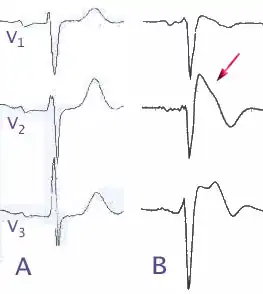

![]() (A) Patrón electrocardiográfico normal en derivaciones precordiales V1, V2, V3. (B) Cambios en el síndrome de Brugada tipo B | ||

El síndrome de Brugada es una enfermedad hereditaria caracterizada por una anormalidad electrocardiográfica (ECG) y un aumento del riesgo de muerte súbita cardíaca. Su nombre se debe a los cardiólogos españoles Pere Brugada, Josep Brugada y Ramón Brugada. Aunque los hallazgos ECG del síndrome de Brugada fueron inicialmente descritos[2] entre supervivientes de parada cardíaca en 1989, no fue hasta 1992 cuando los hermanos Brugada[3] lo reconocieron como una entidad clínica distinta, causante de muerte súbita por fibrilación ventricular (una arritmia cardíaca letal). Las alteraciones electrocardiográficas consisten en una elevación del segmento ST-T en la derivaciones V1 -V3, asociado con bloqueo incompleto o completo de rama derecha y onda T negativa. Al electrocardiograma típico de un paciente con síndrome de Brugada se le conoce como aleta de tiburón.